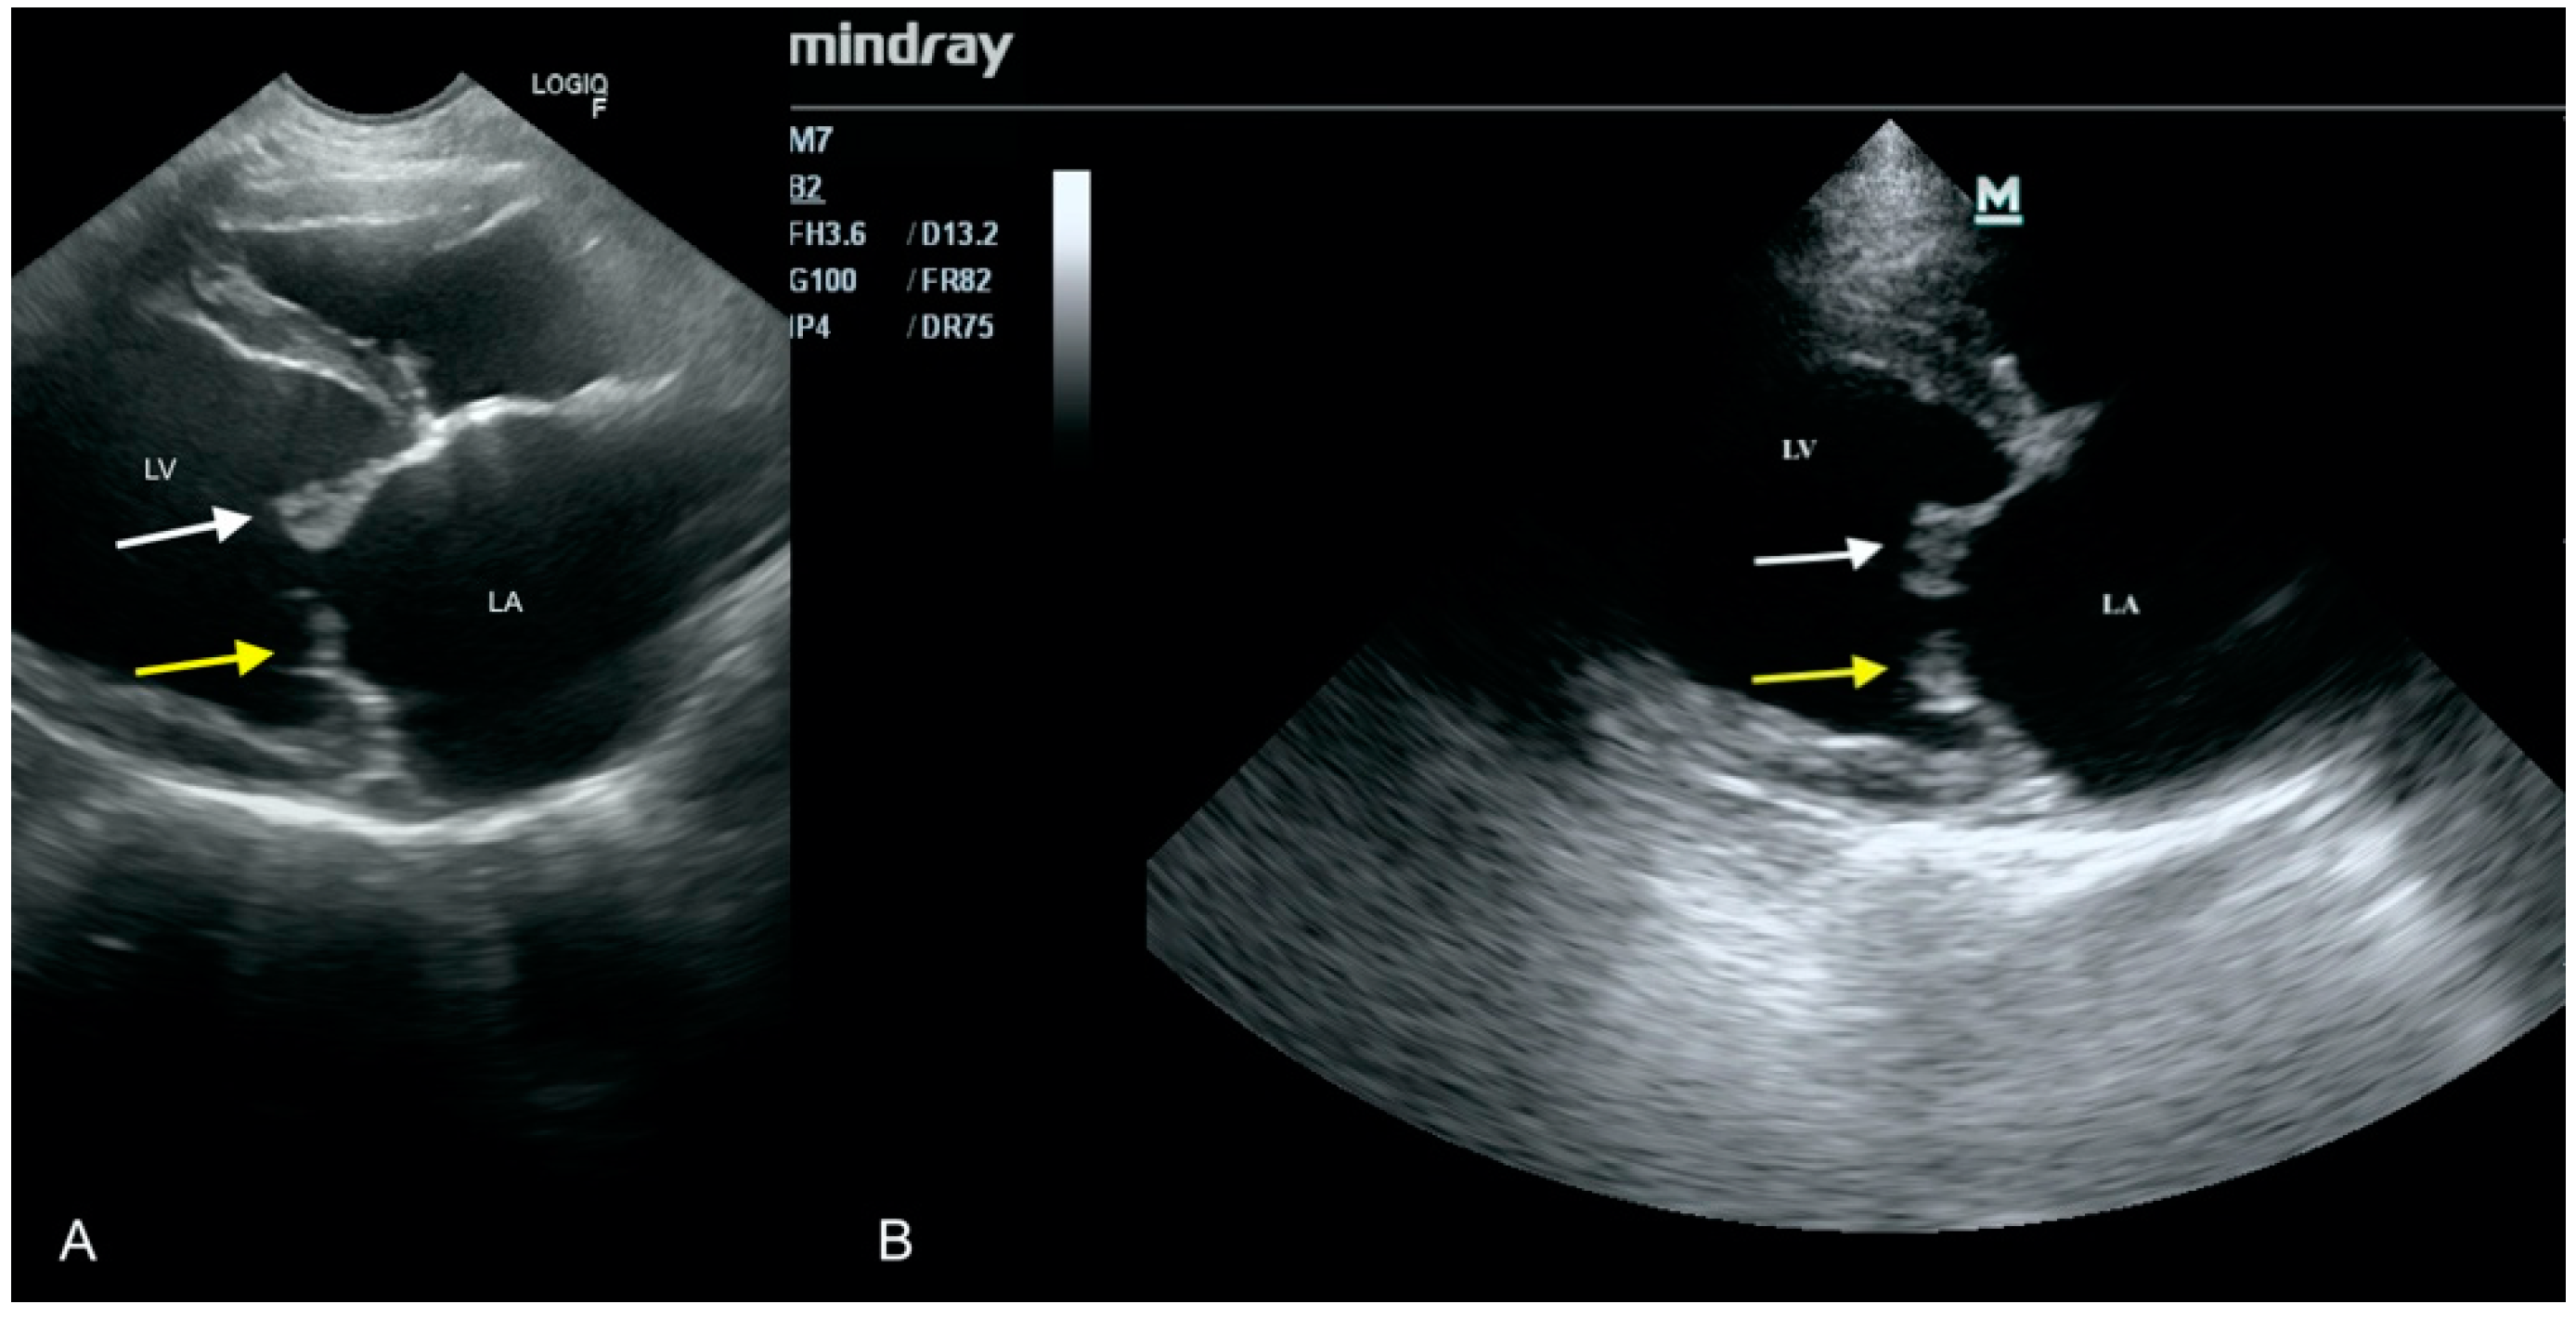

3.5. Case No. 5

3.6. Case No. 6